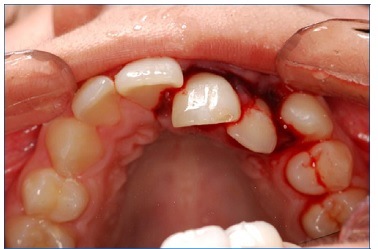

A 15‑year‑old Caucasian female patient was admitted to a private clinic 30 minutes after suffering a severe impact to the oral region during a basketball game at school in 2010. She was not wearing a mouthguard at the moment of the trauma. The intraoral examination revealed a cut on the lower lip and heavy bleeding in the maxilla’s anterior region (Figure 1). Besides, both teeth 21’s (left maxillary central incisor) and 22’s (left maxillary lateral incisor) crowns were slightly dislocated in a palatal and coronal direction, and tooth 21 had an enamel fracture (Figure 2). The patient had vital signs within the normal range and did not have any systemic alterations. Radiographic examination revealed a horizontal root fracture in the middle third of tooth 21 and an enlargement of the periodontal space of tooth 22 (Figure 3). Teeth 21 and 22 did not respond to the cold test with Endo Ice (Maquira, Maringa/PR, Brazil), while the response from teeth 12 (right maxillary lateral incisor), 11 (right maxillary central incisor), and 23 (left maxillary canine) was compatible with a normal pulp. The patient reported pain during the percussion exam on all teeth involved.

The clinical procedures are summarized in chronological order in Table 1. Firstly, under local anesthesia with 2% lidocaine with 1:100,000 epinephrine (Nova DFL, Rio de Janeiro, Brazil), surgical reduction of teeth 21 and 22 was performed (Figure 4). Subsequently, semi‑rigid splitting of teeth 12‑23 was performed with a 0.4‑mm

orthodontic steel wire (Orthometric, Marilia/SP, Brazil) and composite resin (Z100, 3M, Sumare/SP, Brazil) (Figure 4).